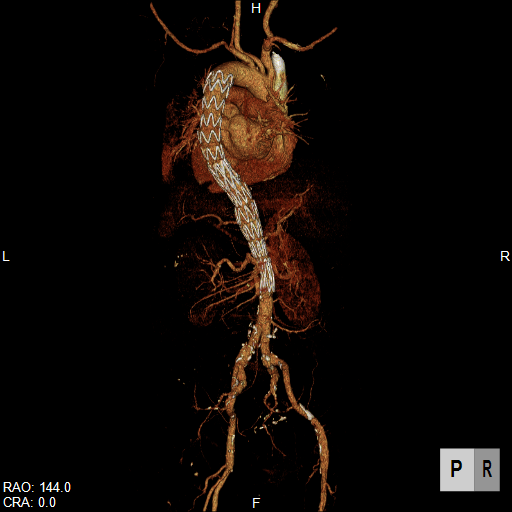

大動脈疾患の診断では、①瘤/解離の範囲と位置、②血流評価、③主要分枝・周囲臓器との関係、④並存疾患の評価、⑤ステントグラフト治療の可能性評価などが必要です。

CTは、体軸方向に分解能の高いボリュームデータを短時間かつ広範囲に得ることができるので、体軸方向に広いスキャンが必要な大動脈疾患の検査に適しています。大動脈病変と分枝動脈の関係だけでなく、分枝動脈自身の評価も可能ですから、手術前シミュレーションや、インフォームドコンセントの参照画像にも有用です。

腹部大動脈瘤へのステントグラフト内挿術評価CT

大動脈解離へのステントグラフト内挿術評価CT